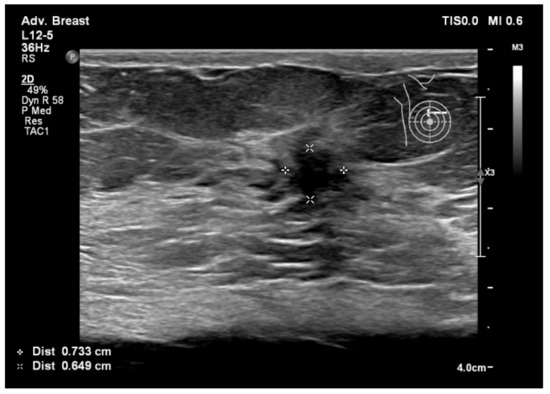

6.1. Characterization of Lesions

9. Types of Lesions Found by Screening with Breast Ultrasound